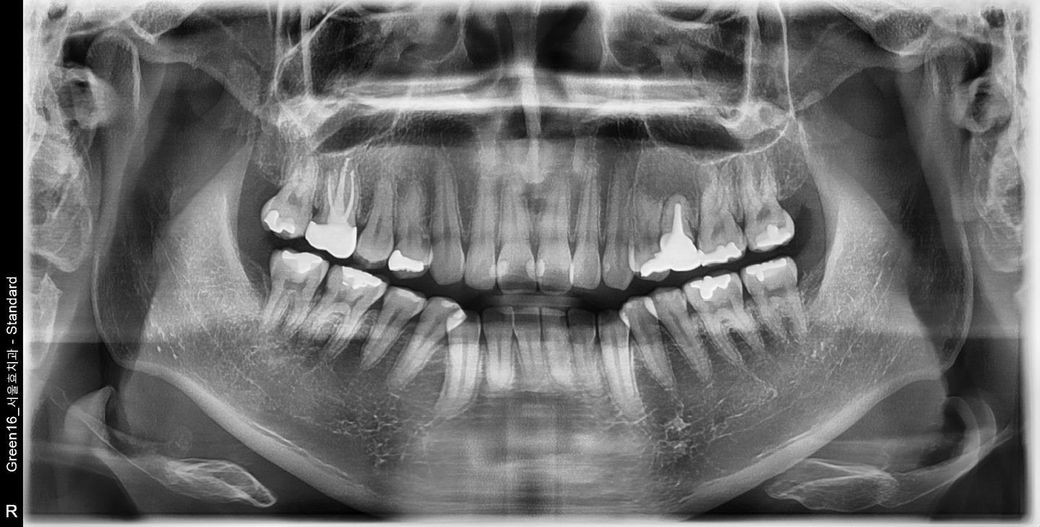

사진 찍고 진료받아보니 뿌리 쪽 잇몸 안에 큰 물혹 염증 같은 게 가득 차 있다고 크기도 많이 크고 상태가 만히 안 좋다 하셔서

일반 치과에서는 치료 못하고 대학병원을 가라고 하셔서요

뿌리의 병수의 크기로 보면 최근에 생긴 것이 아니라 오랜 기간 동안 진행된 것으로 보입니다. 뿌리 끝에 병소가 너무 크다면 신경치료 등으로 해결이 되지 않을 수도 있기 때문에 큰 병원에서의 치료가 필요할 수 있습니다. 자세한 확인을 위해서 치과에서 진료를 받아보세요.

안녕하세요 치과의사 김철진입니다. 치아때문에 생긴 염증이라면 치근단 절제술을 해볼수 잇지만 낭종이라면 수술적으로 제거를 하셔야될것같습니다.

ct등 추가 사진을 찍어보고 판단하면 더 좋을 것 같습니다.

일단 주어진.. 상태만 보고 판단하자면 씌운 치아의 내부파절이 의심되며

해당 치아를 발치하고 내부 염증 제거 후 골이식.

4~6개월 충분히 기다린 다음 임플란트 진행할 것 같습니다.